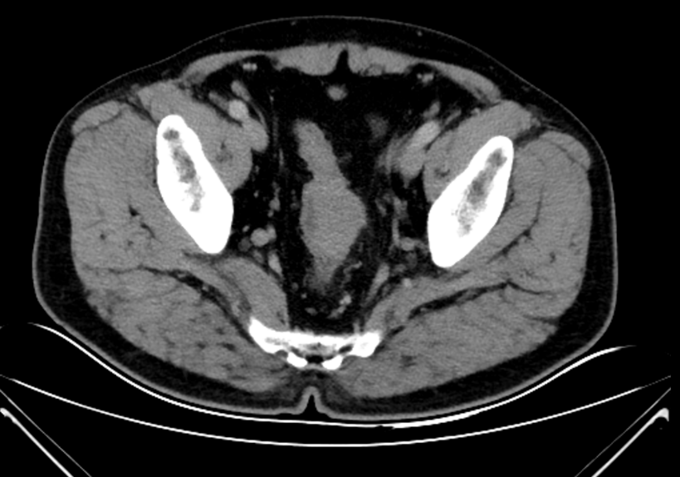

查体:腹平坦,未见胃肠型及蠕动波,未见腹壁静脉曲张。全腹软,未触及腹部肿块,压痛(-),反跳痛(-),肌紧张(-)。肝脾肋下未触及,Murphy’s 征(-),肝区叩击痛(-),移动性浊音(-)。肾区叩击痛(-)。肠鸣音正常,4次/分。肘膝位,肛门进指顺利,进指约7cm,未触及明确肿物,退指指套无染血。 辅助检查:马应龙肛肠医院肠镜检查显示:距离肛门60cm30cm见两枚大小约0.3*0.2cm息肉,表面光滑,广基、无蒂、无色泽略红,距肛门15cm处可见一半环行菜花样粘膜隆起。表面凹凸不平,出血、糜烂与污秽交织在一起,隆起向腔内生长,至管腔狭窄,镜身未通过,取病理5块。 术前腹部CT:乙状结肠下段肠壁增厚